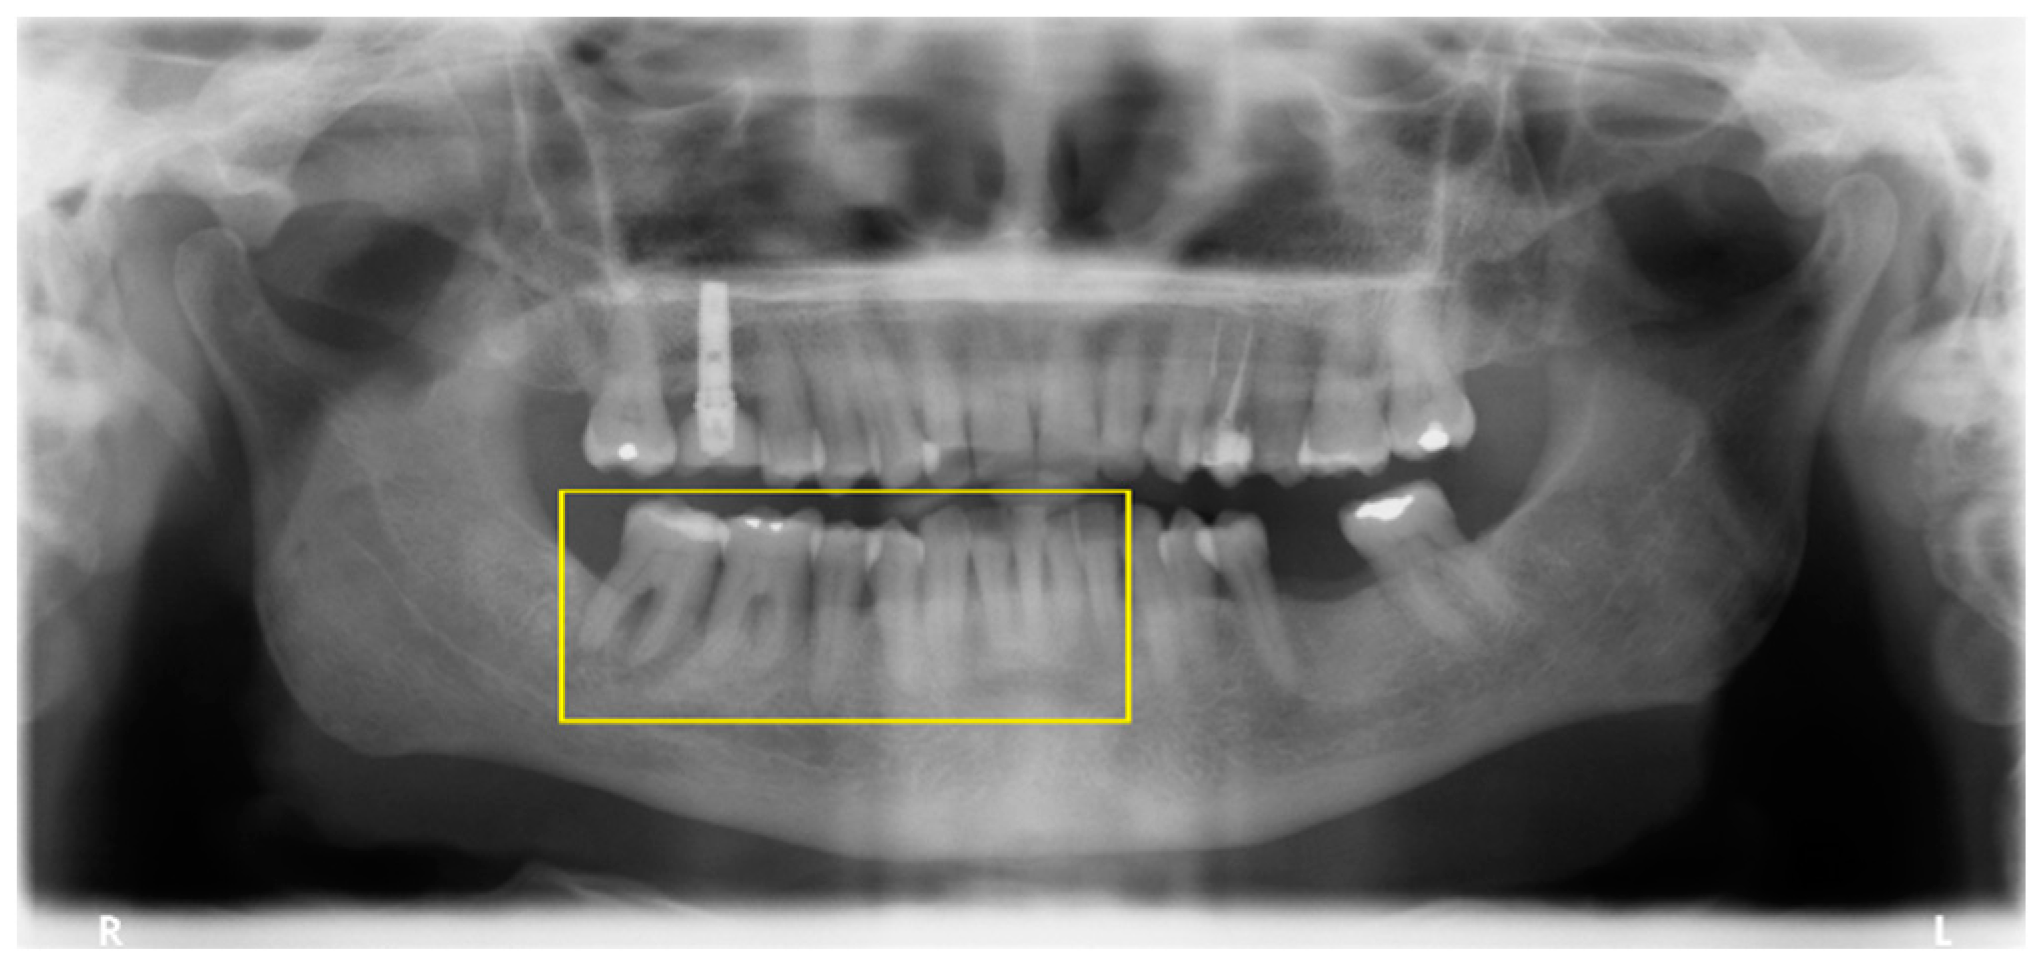

3.3. Risk Score

| Risk Score (Sum of Points) | Risk Group and Predicted Probability Estimated from the Risk Score | Within Group Incidence of Periodontitis | Observed Incidence of Periodontitis |

| −1–0 points | <26.6%—Low risk (<0.5 preanalysis risk) | 14/61 = 23% | 14/344 = 4.1% |

| 1–2 points | 26.6–53.2%—Moderate risk (0.5 to <1 times preanalysis risk) | 74/159 = 46.5% | 74/344 = 21.5% |

| ≥3 points | > 53.2%—High risk (>1 times preanalysis risk) | 95/124 = 76.6% | 95/344 = 27.6% |

| C-statistic (95% confidence interval) = 0.75 (0.70; 0.80); p < 0.001 | |||

| Variables | Status | Score |

|---|---|---|

| Age less than 53 years | No | 0 |

| Smoker | No | 0 |

| Less than two observations in the first year of follow-up | No | 0 |

| Presence of gingivitis | Yes | 2 |

| Presence of sub-gingival calculus | Yes | 1 |

| History of periodontitis | Yes | 1 |

| Total points | 4 | |

| Risk profile | High risk | |

| Probability of periodontitis | >53.2% | |